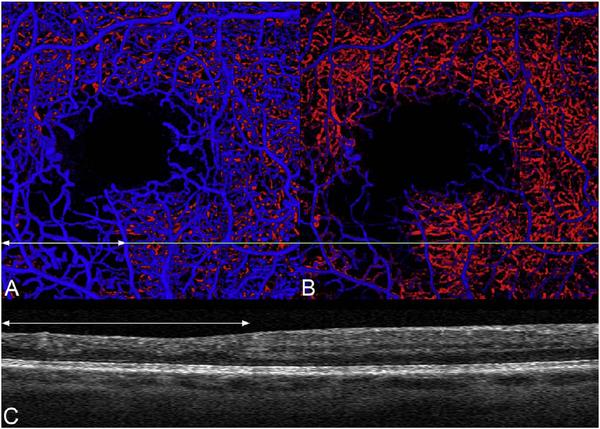

Optical coherence tomography (OCT) was one of the biggest advances in ophthalmic imaging. Building on that platform, OCT angiography (OCTA) provides depth resolved images of blood flow in the retina and choroid with levels of detail far exceeding that obtained with older forms of imaging. This new modality is challenging because of the need for new equipment and processing techniques, current limitations of imaging capability, and rapid advancements in both imaging and in our understanding of the imaging and applicable pathophysiology of the retina and choroid. These factors lead to a steep learning curve, even for those with a working understanding dye-based ocular angiography. All for a method of imaging that is a little more than 10 years old. This review begins with a historical account of the development of OCTA, and the methods used in OCTA, including signal processing, image generation, and display techniques. This forms the basis to understand what OCTA images show as well as how image artifacts arise. The anatomy and imaging of specific vascular layers of the eye are reviewed. The integration of OCTA in multimodal imaging in the evaluation of retinal vascular occlusive diseases, diabetic retinopathy, uveitis, inherited diseases, age-related macular degeneration, and disorders of the optic nerve is presented. OCTA is an exciting, disruptive technology. Its use is rapidly expanding in clinical practice as well as for research into the pathophysiology of diseases of the posterior pole.

光学相干断层扫描(OCT)是眼科成像领域的重大突破之一。在此基础上,OCT 血管造影术(OCTA)提供了视网膜和脉络膜血流的深度分辨图像,其细节水平远远超过了旧的成像方式。这种新的模式具有挑战性,因为需要新的设备和处理技术,目前成像能力的限制,以及成像和对视网膜和脉络膜成像及适用病理生理学的理解的快速发展。这些因素导致学习曲线陡峭,即使对于那些对基于染料的眼部血管造影术有一定了解的人来说也是如此。所有这些都是为了一种成像方法,它的历史还不到 10 年。这篇综述从 OCTA 的发展历史和 OCTA 中使用的方法开始,包括信号处理、图像生成和显示技术。这是理解 OCTA 图像显示内容以及图像伪影产生原因的基础。本文还回顾了眼部特定血管层的解剖结构和成像。介绍了 OCTA 在评估视网膜血管阻塞性疾病、糖尿病性视网膜病变、葡萄膜炎、遗传性疾病、年龄相关性黄斑变性和视神经疾病的多模态成像中的整合。OCTA 是一种令人兴奋的、颠覆性的技术。它在临床实践中的应用以及对后极部疾病病理生理学的研究中迅速扩展。